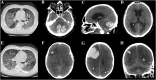

Background: Italy is one of the most affected countries by the coronavirus disease 2019 (COVID-19). The responsible pathogen is named severe acute respiratory syndrome coronavirus (SARS-CoV-2). The clinical spectrum ranges from asymptomatic infection to severe pneumonia, leading to intensive care unit admission. Evidence of cerebrovascular complications associated with SARS-CoV-2 is limited. We herein report six patients who developed acute stroke during COVID-19 infection.

Methods: A retrospective case series of patients diagnosed with COVID-19 using reverse-transcriptase polymerase chain reaction (RT-PCR) on nasopharyngeal swabs, who developed clinical and neuroimaging evidence of acute stroke during SARS-CoV-2 infection.

Results: Six patients were identified (5 men); median age was 69 years (range 57-82). Stroke subtypes were ischemic (4, 67%) and hemorrhagic (2, 33%). All patients but one had pre-existing vascular risk factors. One patient developed encephalopathy prior to stroke, characterized by focal seizures and behavioral abnormalities. COVID-19-related pneumonia was severe (i.e., requiring critical care support) in 5/6 cases (83%). Liver enzyme alteration and lactate dehydrogenase (LDH) elevation were registered in all cases. Four patients (67%) manifested acute kidney failure prior to stroke. Four patients (67%) had abnormal coagulation tests. The outcome was poor in the majority of the patients: five died (83%) and the remaining one (17%) remained severely neurologically affected (mRS: 4).

Conclusions: Both ischemic and hemorrhagic stroke can complicate the course of COVI-19 infection. In our series, stroke developed mostly in patients with severe pneumonia and multiorgan failure, liver enzymes and LDH were markedly increased in all cases, and the outcome was poor.